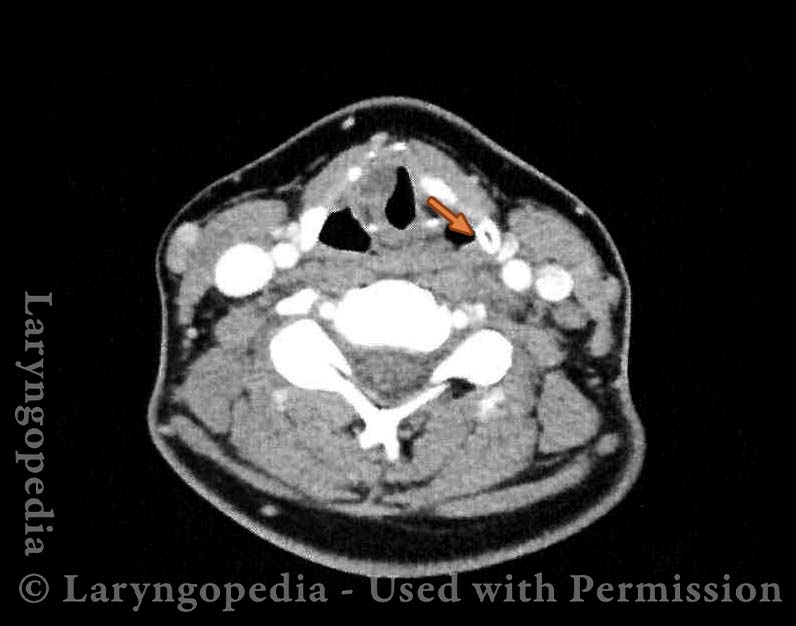

CT of cyst (4 of 18)